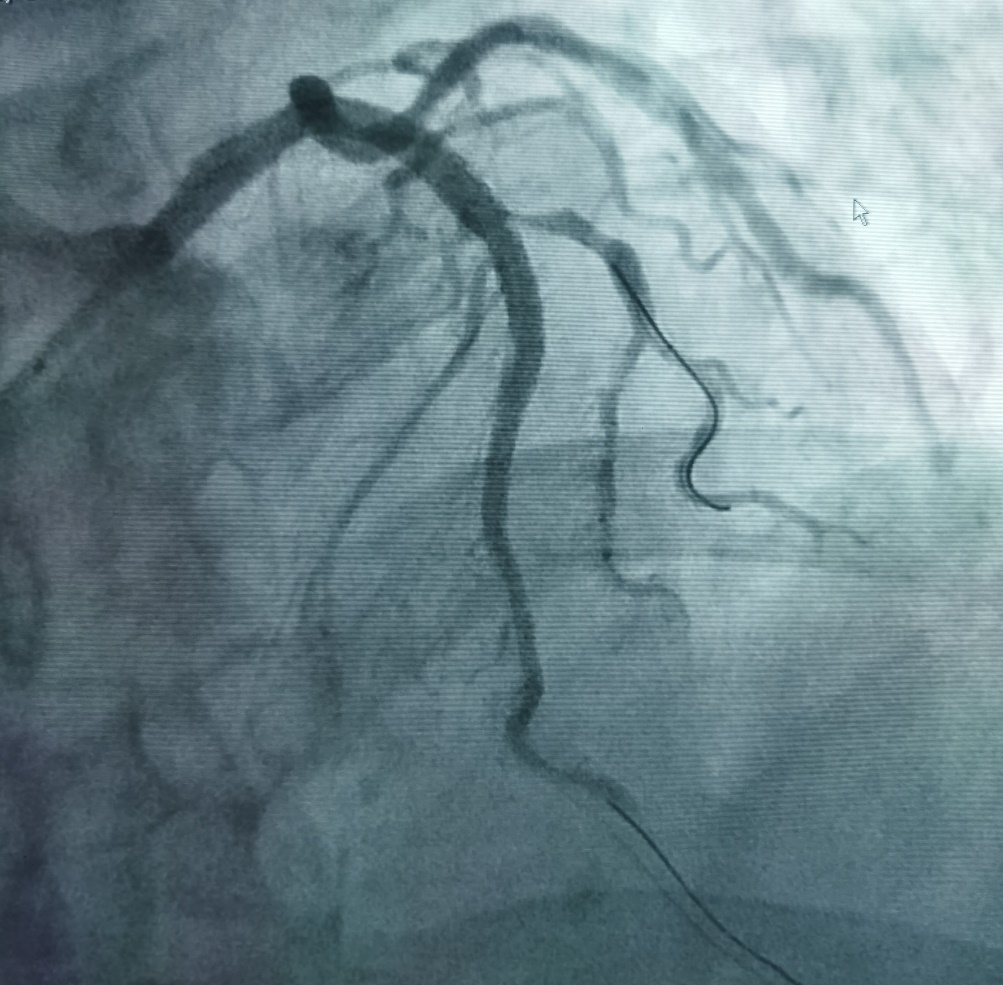

患者吴先生,68岁,有吸烟史20年,高血压史20年,持续胸闷1年,1月前剧烈活动后出现胸闷,持续数小时可自行缓解,入院后诊断为不稳定型心绞痛。冠脉造影显示冠脉左前降支开口可见50%狭窄,近端可见95%偏心狭窄,局部瘤样扩张,可见钙化影(图1),此种情况极易造成支架膨胀不全。据此杨清教授和徐绍鹏教授果断选择3.0 x 12mm Shockwave IVL冲击波球囊对近段钙化病变进行4个周期40个脉冲的预处理(图2),而后植入支架,达到了理想的支架膨胀结果(见图3)。

图2 X线下IVL球囊扩张图像及示意图